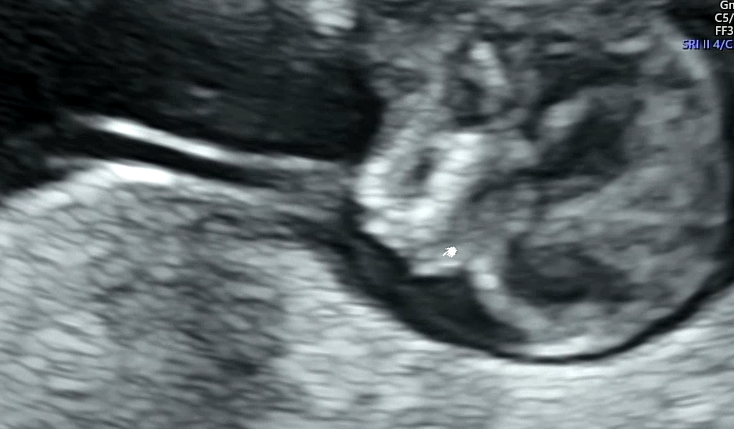

8주 검진 이후로 지난한 4주를 지나 12주차가 되었다. 오랜만에 보러가는 딱붕이와 긴장되는 1차 기형아 검사.

처음으로 배 초음파를 했다. 너무 좋았음! 질 초음파는 힘드로...

배 초음파를 하는데 태아가 꿈틀꿈틀 열심히도 움직였다. 백숙같은 몸매를 뽐내는 딱붕스

1차 기형아 검사의 포인트!

목투명대의 두께와 콧대의 유무이다.

태아가 너무 움직여서 심장소리와 목 투명대 길이를 재는데 애를 먹었다. 초음파를 보면서 귀엽다는 생각이 드는 나는 엄마가 되어가는 건가...!

목 투명대는 1.46mm가 나와서 정상이라고 하셨다. 1~3mm 사이면 정상 범위이고 3mm이상부터는 다운증후군 고위험군으로 판단된다. 그런데 2.5mm 대 정도도 걱정스러운 정도라서 좀 더 정확한 검사인 니프티 검사를 해보자고 하기도 한다.

콧대가 없으면 안면장애나 다운증후군이 의심되는데 콧대도 발견되었다!

출혈도 안보이고 아이도 건강하게 있는 걸 보고는 의사선생님이 "다행히 자리를 잘 잡았네요. 건강하게 잘 자라고 있습니다. 이제부터 안정기입니다" 라고 하는 말에 어찌나 마음이 놓이던지...ㅠ 의사쌤이 별 말을 안하셔서 몰랐는데 걱정 시키지 않게 하시려고 했다는게 느껴지는 검진이었다... 감사해요ㅠㅠ

(성별은 알 수 없었다. 태아가 별다른 힌트를 보여주지 않았음)